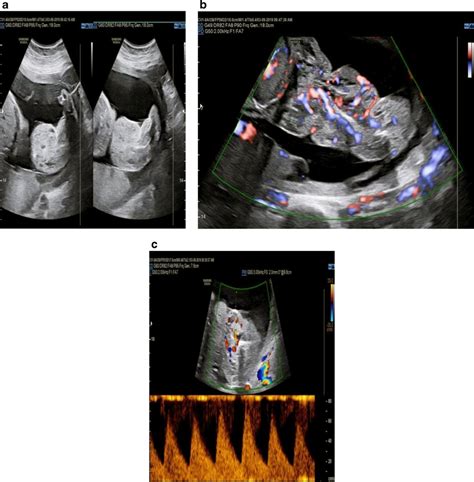

Sonography at 28 Weeks

An ultrasound at this stage can provide comprehensive insights into the fetus’s development, including:

• Anatomical Survey: This detailed examination can confirm that all major organs and body parts are present and functioning correctly. It includes checking the heart’s structure and function, brain development, the presence of kidneys and bladder function, and the limbs and digits for any abnormalities.

• Growth Parameters: Measurements of the fetus’s size, from the head to the abdomen and femur, help assess its growth rate and detect any deviations from the expected growth curve.

• Placenta and Amniotic Fluid Assessment: The health and function of the placenta, as well as the volume of amniotic fluid surrounding the fetus, are crucial indicators of fetal well-being. Abnormalities here could indicate issues with the fetus’s nutrition and waste removal.